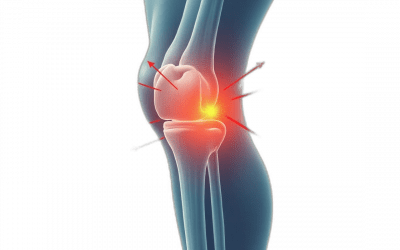

Dolor en la Parte Interna de la Rodilla: Causas, Tratamiento y Readaptación Deportiva

El dolor en la parte interna de la rodilla es una molestia que afecta a muchas personas, desde deportistas habituales hasta quienes llevan un estilo de vida más sedentario. Este tipo de dolor puede limitar enormemente la movilidad, afectar tu rendimiento físico y...

Rodilla del Corredor: Soluciona tu Dolor de Rodilla Después de Correr

La rodilla del corredor es una lesión común especialmente en corredores principiantes, mostrándose como un intenso dolor de rodilla después de correr y que puede afectar enormemente física y mentalmente, haciendo que se llegue abandonar la práctica deportiva devido a...

Rehabilitación de Rodilla: guía integral basada en la ciencia

La rehabilitación de rodilla es un proceso esencial para recuperar la movilidad y funcionalidad tras lesiones o intervenciones quirúrgicas, siendo cada vez más importante tanto en entornos clínicos como a la hora de realizar una rehabilitación de rodilla en casa. Con...